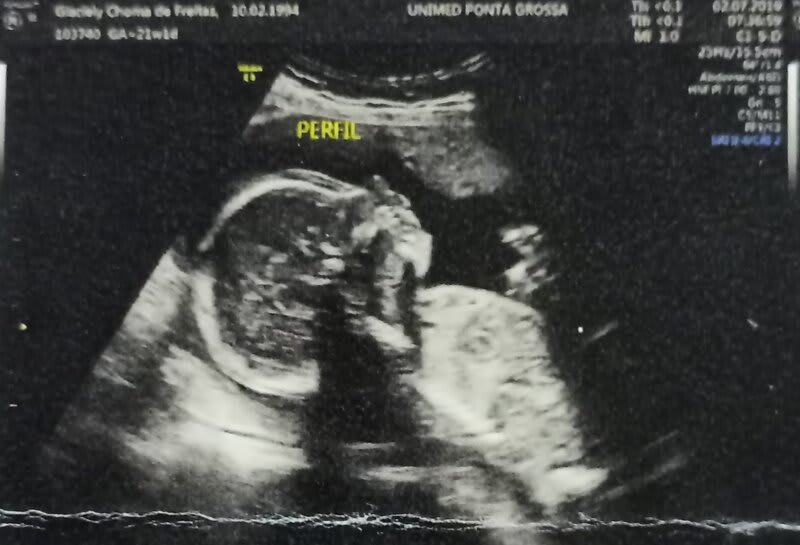

“No início de 2019 decidimos engravidar e para nossa surpresa foi super rápido, fizemos os primeiros exames e até então estavam todos bem. Tínhamos o sonho de ser pais de menina, fizemos a sexagem fetal e descobrimos que a nossa menininha estava a caminho, nossa tão esperada e sonhada Julia.

No primeiro exame morfológico descobrimos algumas alterações, nosso mundo desabou, o medo tomou conta de nós, será que nossa tão sonhada menininha estava em perigo? Então começamos a busca para descobrir o que ela tinha, a médica de início achou que fosse Síndrome de Down, realizamos um exame que é chamado de amniocentese, nesse exame é retirado um líquido da placenta para verificar qual doença o bebê tem.

O resultado saiu e nossa menininha não tinha nenhuma doença cromossômica, porém, ela estava com má formação em alguns órgãos. A cada ultrassom era uma notícia pior, a médica disse para não fazermos chá de bebê ou enxoval, que o meu corpo estava rejeitando o feto e seria necessário aguardar para ver até onde a gestação iria.

No dia 18 de Julho de 2019 entrei em trabalho de parto e a Julia nasceu prematura de de 22 semanas pesando 700 gramas, infelizmente ela ficou apenas 30 minutos viva e acabou falecendo. Nesse meio tempo eu tive complicações no parto (acretismo placentário), a médica não conseguiu tirar minha placenta, tive uma hemorragia e se meu útero não fosse removido eu morreria. Passei por uma histerectomia de emergência, foi um procedimento complicado, perdi muito sangue, realmente foi por um milagre que eu sobrevivi.